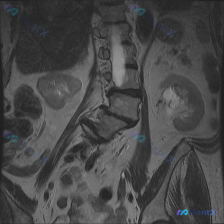

整理到一张腹部MRI T2加权冠状位的影像资料,先不放临床病史,只看图像大家第一眼会关注到什么?

影像里能看到的几个关键点先提一下:

- 脊柱序列不太对,腰椎段有明显的侧向弯曲

- 多个椎间盘在T2上信号减低,椎间隙也有窄的地方

- 中下段好像有椎间盘向后突,硬膜囊前缘受压变窄

- 椎体边缘能看到一些低信号的突起

肾脏这些腹部实质脏器看起来倒是没什么特别的异常高信号。